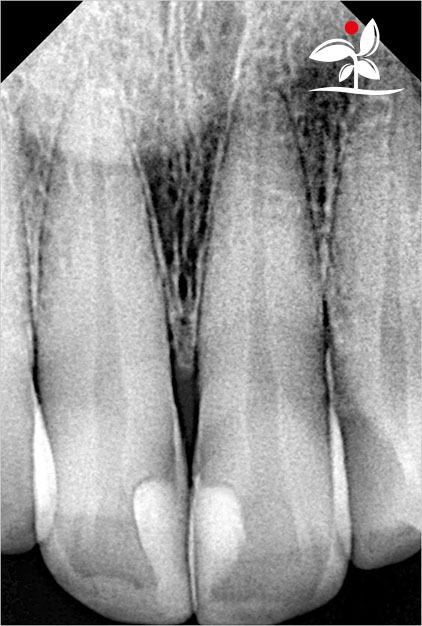

Restoration of Class IV Lesions using Naturomimetic Layering Technique (NLT) and Bioactive Restorative Materials

With the growing awareness about the health, function and aesthetic benefits of preserving natural tooth structure, patients are now globally demanding for aesthetic dentistry with minimally invasive procedures that has a low biological cost. This public demand has encouraged logical clinicians to adopt to the minimally invasive cosmetic dentistry (MiCD) concept and its treatment protocol [1] in their practice. The author has been using MiCD concept and its treatment protocols since 2017, which

include the methods of treatment that are simple, fast, predictable and healthy. In aesthetic restoration, the tooth color restorative materials placement technique is one of the most challenging, confusing and frustrating areas to learn owing to the multiple techniques that have been proposed by many clinicians and replicating such techniques in practice is not always as easy as they are marketed in dentistry. Natural teeth are complex in structure and hard to simulate due distribution of colors through enamel and dentin [2]. Aesthetic restoration strategies should follow proper understanding of defects, right selection of restorative materials along with their proper application, finishing, texturing and polishing [2].